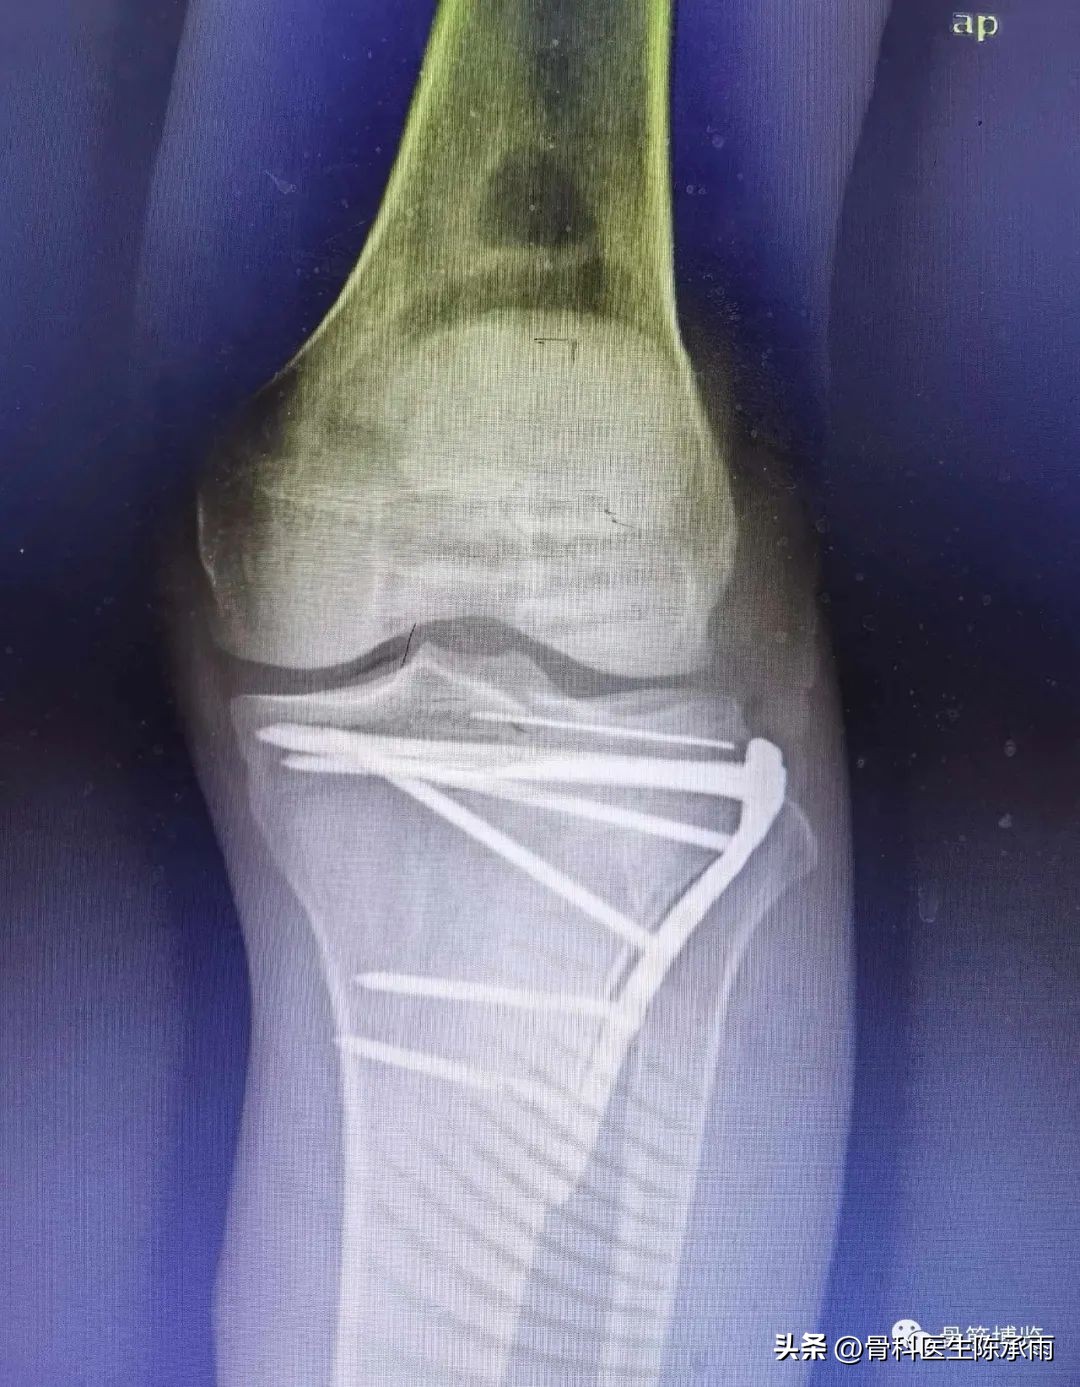

1例

2例

3例

4例

5例

6例

7例